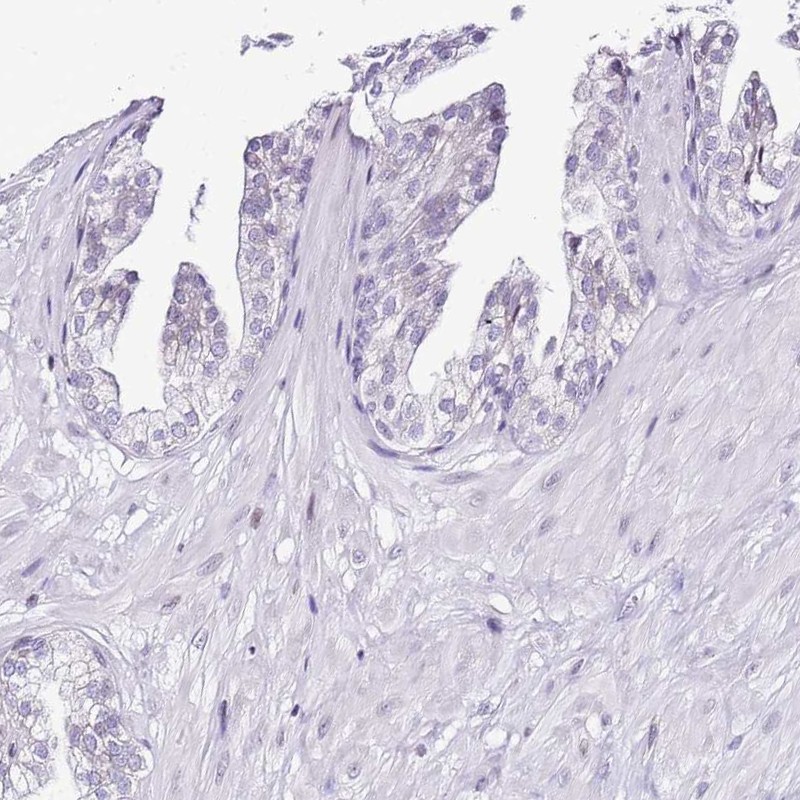

Immunohistochemistry analysis in human cervix, uterine and prostate tissues using Anti-PRR15 antibody. Corresponding PRR15 RNA-seq data are presented for the same tissues.